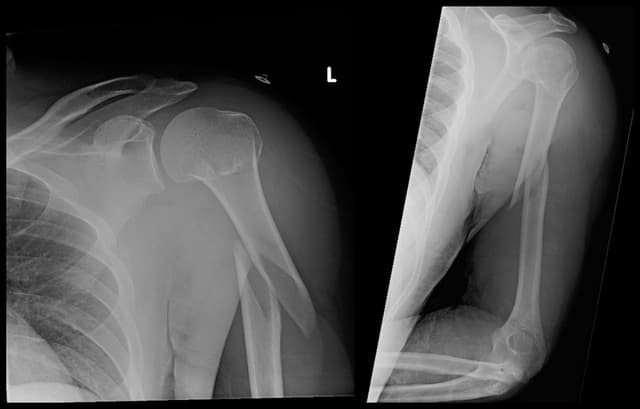

Segmental Humerus ORIF

Imaging

Pre-op